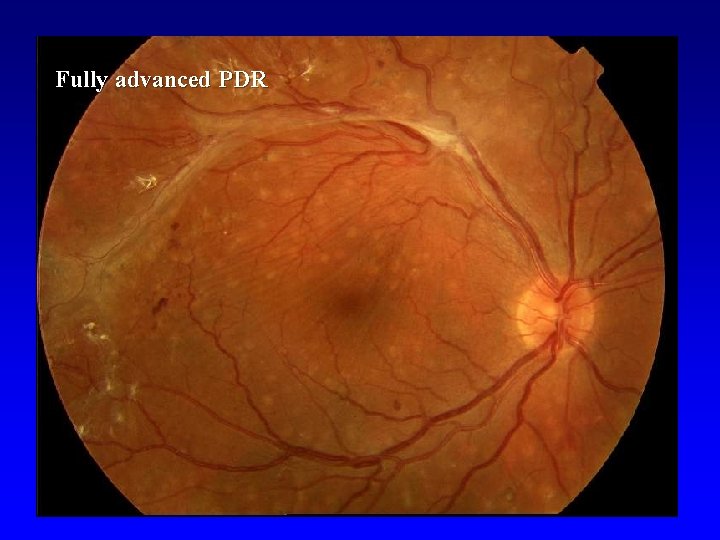

Proliferative DR (PDR) • • • Light Intermediate Fully advanced VH- vitreous hemorrhage, PRHpreretinal hemorhage, TRD- retinal detachment at center of macula

Fully advanced PDR